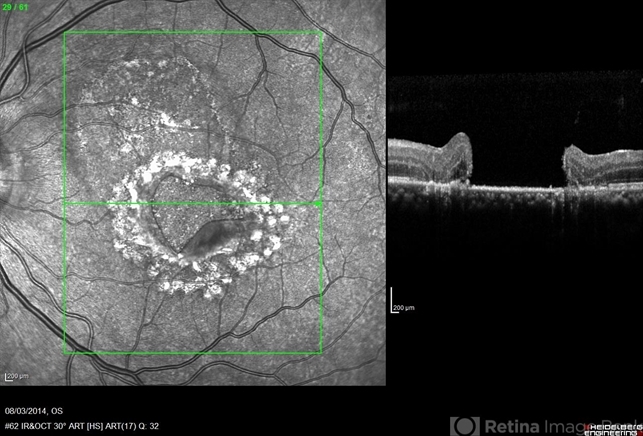

- macular hole, optical coherence tomography (OCT)

Optical coherence tomography system

Heidelberg HRA + OCT Spectralis - Description

- OCT a 40-year-old man with macular tear (had a photocoagulation laser).